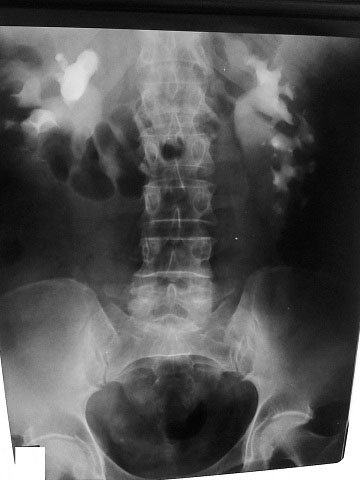

Рентгенолог сказал, что есть сдавление правого мочеточника извне на уровне с\3. Снимки не видела. Думаю, после обеда смогу их увидеть и выложить. Хочу её после обеда, как освободится аппарат, пересмотреть.

L3 ?Anastasia писал(а):Рентгенолог сказал, что есть сдавление правого мочеточника извне на уровне с\3. Снимки не видела. Думаю, после обеда смогу их увидеть и выложить. Хочу её после обеда, как освободится аппарат, пересмотреть.

средней трети мочеточника

Сори за задержку- технические трудности.

Вот снимки:

По УЗИ получается что эта штука должна быть примерно здесь - указано стрелкой - или чуть ниже.

Еще желательно проинспектировать нижнюю треть правого мочеточника при наполненном мочевом пузыре - непонятна атония мочеточника на всем протяжении, нужно искать причину.